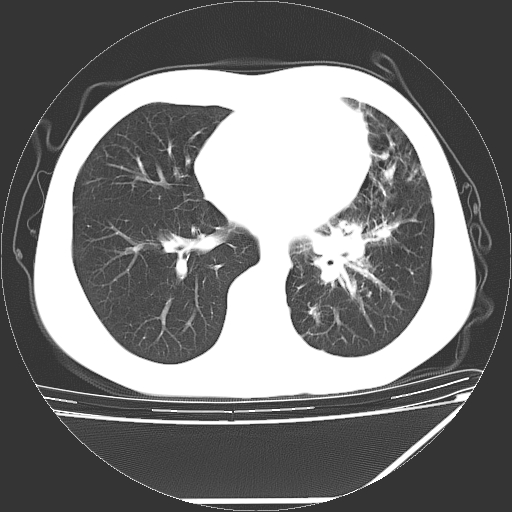

男,13岁,咳嗽、咳痰伴发热一周。

中上纵隔见多枚淋巴结肿大,部分相互融合成团片,左肺门增大,上叶支气管变窄,肺内多处斑片状 索条状及棉絮状致密影。临床“男,13岁,咳嗽、咳痰伴发热一周。”首先考虑:原发综合征!不除外淋巴瘤可能!

纵隔多发肿大淋巴结,部份有融合改变。双肺血管气管束增厚,以肺门为中心向外周散发,以左肺下叶为明显。考虑淋巴瘤可能性大。不除外原发综合征。

中上纵隔见多枚淋巴结肿大,部分相互融合成团片,左肺门增大,上叶支气管变窄,左肺支气管血管束增粗,可见磨玻璃样影。临床“男,13岁,咳嗽、咳痰伴发热一周。”首先考虑:淋巴瘤可能性大!

中上纵隔见多枚淋巴结肿大,部分相互融合成团片,纵隔内脂肪间隙模糊,左肺门增大,上叶支气管变窄,左肺支气管血管束增粗,可见磨玻璃样影。考虑纵隔淋巴管炎